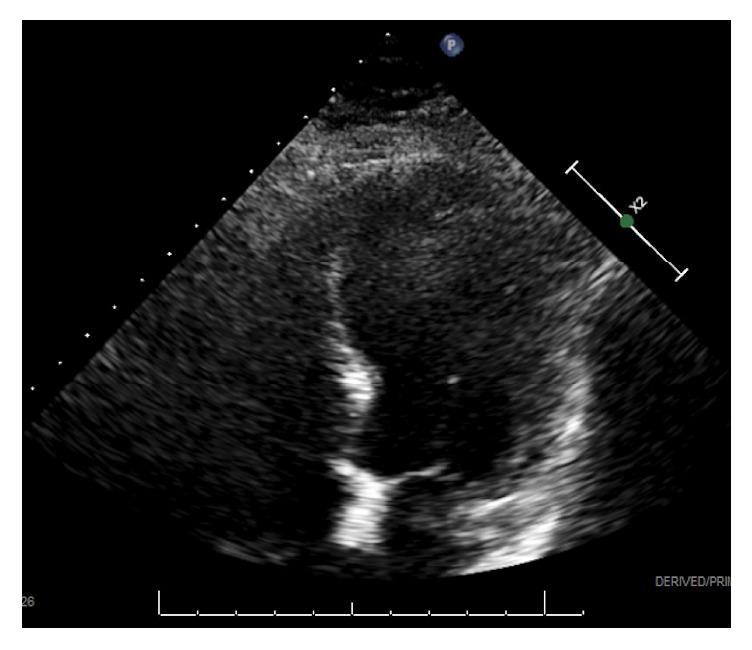

Takotsubo Cardiomyopathy (TCM) should be considered in the differential diagnosis for patients with cardiovascular symptoms not only following emotional trauma but also following motor vehicle accidents. A 45-year-old woman presented with chest pain following a motor vehicle accident. While she had an elevated troponin level and an extensive history of cardiac disease, her electrocardiogram was normal. Echocardiogram, however, demonstrated transiently reduced left ventricular systolic function with mid to apical hypokinesis consistent with TCM. We emphasize the use of a diagnostic score and point of care focused cardiac ultrasound (FOCUS) to expedite the recognition, evaluation, and treatment of suspected TCM in an Emergency Department setting.

对于出现心血管症状的患者,无论是在情绪创伤后还是在机动车事故后,鉴别诊断时都应考虑应激性心肌病(TCM)。一名45岁女性在机动车事故后出现胸痛。尽管她肌钙蛋白水平升高且有广泛的心脏病史,但其心电图正常。然而,超声心动图显示左心室收缩功能短暂降低,伴有中至心尖运动减弱,符合应激性心肌病表现。我们强调在急诊科环境中使用诊断评分和即时床旁心脏超声(FOCUS),以加快对疑似应激性心肌病的识别、评估和治疗。